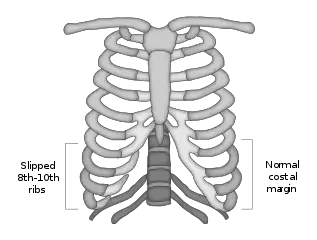

| Illustration of slipping rib syndrome | |

| Treatment | Analgesics, injections, surgery |

Slipping rib syndrome (SRS) is a condition in which the interchondral ligaments are weakened or disrupted and have increased laxity, causing the costal cartilage tips to subluxate (partially dislocate). This results in pain or discomfort due to pinched or irritated intercostal nerves, straining of the intercostal muscles, and inflammation. The condition affects the 8th, 9th, and 10th ribs, referred to as the false ribs, with the 10th rib most commonly affected.